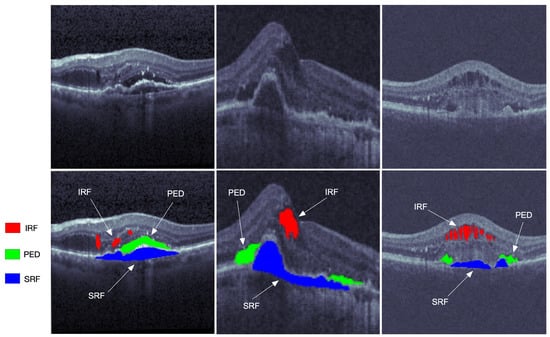

| IRF | Intraretinal Fluid |

| PED | Pigment Epithelial Detachment |

| SRF | Subretinal Fluid |